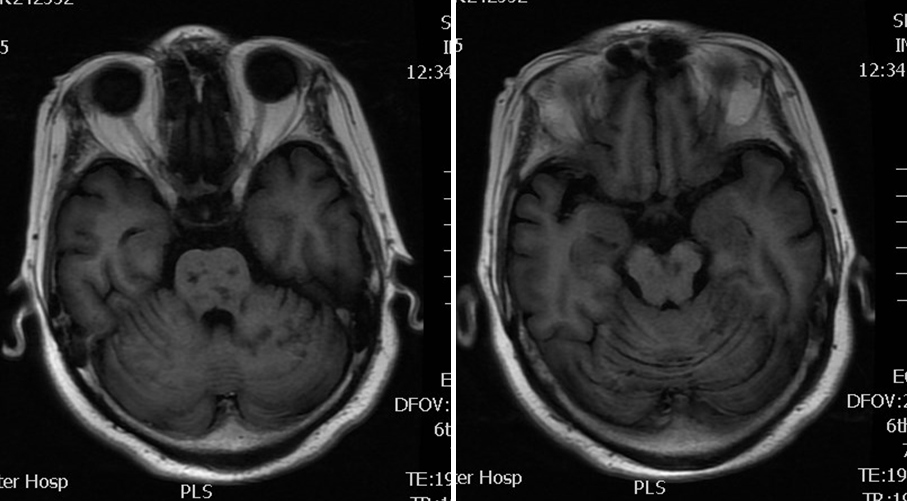

入院影像检查

导丝怎么扩【载药时代 球扩天下】NOVA DES®颅内药物洗脱支架在基底动脉近端重度狭窄的应用—西安市中心医院使用体会一例!_https://www.jmylbn.com_新闻资讯_第4张

MRA

导丝怎么扩【载药时代 球扩天下】NOVA DES®颅内药物洗脱支架在基底动脉近端重度狭窄的应用—西安市中心医院使用体会一例!_https://www.jmylbn.com_新闻资讯_第5张

DWI

重要影像结论:双侧小脑半球、脑干、右侧枕叶多发脑梗死;基底动脉、右侧大脑后动脉闭塞。